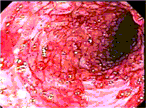

Diffuse vascular malformation of large intestine clinically and radiologically misdiagnosed as ulcerative colitis

Dilasma Ghartimagar and others

Journal of Surgical Case Reports, Volume 2017, Issue 2, February 2017, rjx016, https://doi.org/10.1093/jscr/rjx016